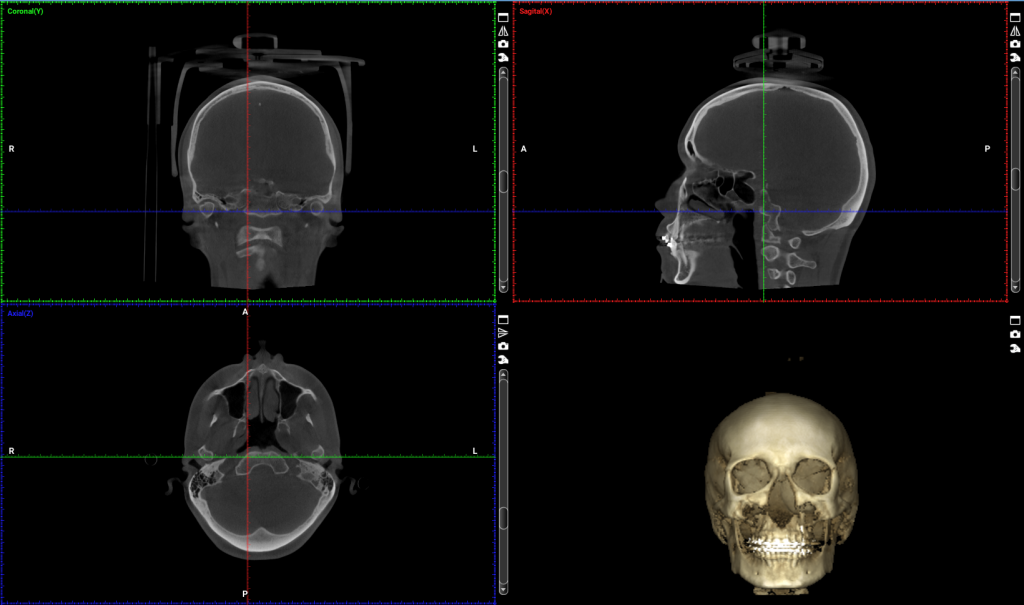

El CBCT 3D permite obtener una imagen tridimensional completa del esqueleto facial, ofreciendo información milimétrica sobre la posición de huesos, dientes y articulaciones.

Gracias a esta tecnología, los cirujanos pueden simular movimientos óseos, evaluar posibles interferencias y anticipar los resultados estéticos y funcionales.

- Reconstrucciones 3D realistas del cráneo y la mandíbula.

- Evaluación de asimetrías faciales y relación entre maxilares.

Imagen 1: Vista coronal de CBCT de cráneo completo para cirugía ortognática (FOV 23×26). Imagen aportada por RD3D.

Imagen 2: Vista sagital de CBCT de cráneo completo para cirugía ortognática (FOV 23×26). Imagen aportada por RD3D.

Imagen 3: Vista axial o transversal de CBCT de cráneo completo para cirugía ortognática (FOV 23×26). Imagen aportada por RD3D.